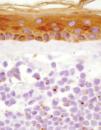

Fig. 2.--Detalle de la tumoración en dermis superficial, con una evidente positividad paranuclear en gotas con citoqueratinas (AE1-AE2).

El estudio histopatológico mostró infiltración tumoral de la dermis por células redondeadas de tamaño pequeño e intermedio, con escaso citoplasma, y que se disponían de forma compacta en nidos. El estudio inmunohistoquímico demostró positividad para citoqueratinas (AE1-AE2) y neurofilamentos, con un patrón paranuclear en gotas (fig. 2). También se obtuvo positividad con las tinciones para sinaptofisina y cromogranina A.